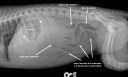

C’était quoi tout ça dans l’estomac ?

RadioQuiz 16 – Réponse

RadioQuiz 15 – Réponse

RadioQuiz 14 – Réponse